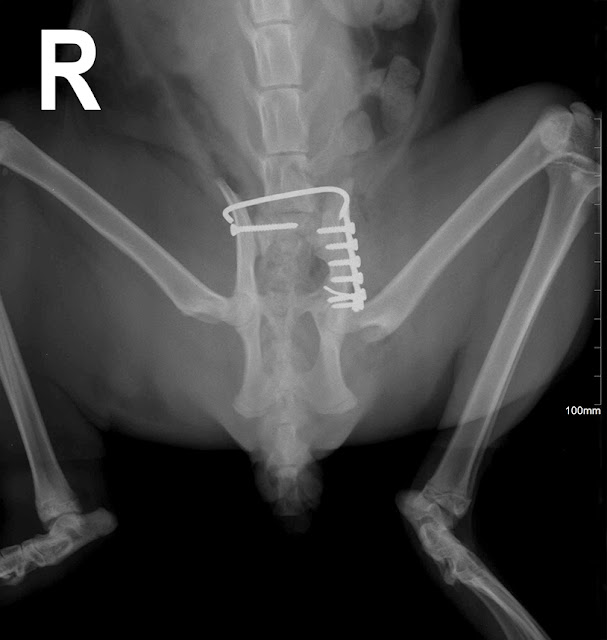

Veamos las radiografías de control post operatorio:

Como puede apreciarse en las imágenes anteriores se colocó un

pin intramedular y dos placas de bloqueo, para tornillos de 2,7mm, colocando

una primera placa en cara medial, y luego una segunda placa en la cara lateral

del húmero.

Valorando un poco el resultado, debo decir que el clavo

intramedular fué un poco difícil de colocar al principio, pero luego fue muy

útil porque facilitó mucho la reducción y la colocación de la primera placa en

la cara medial. Probablemente el clavo debería ser un poco más largo, de hecho,

cuesta verlo en la primera imagen post operatoria, aunque en la vista lateral

se aprecia mejor, y creo que es una gran aportación tanto para la reducción

como para la estabilización de la fractura.